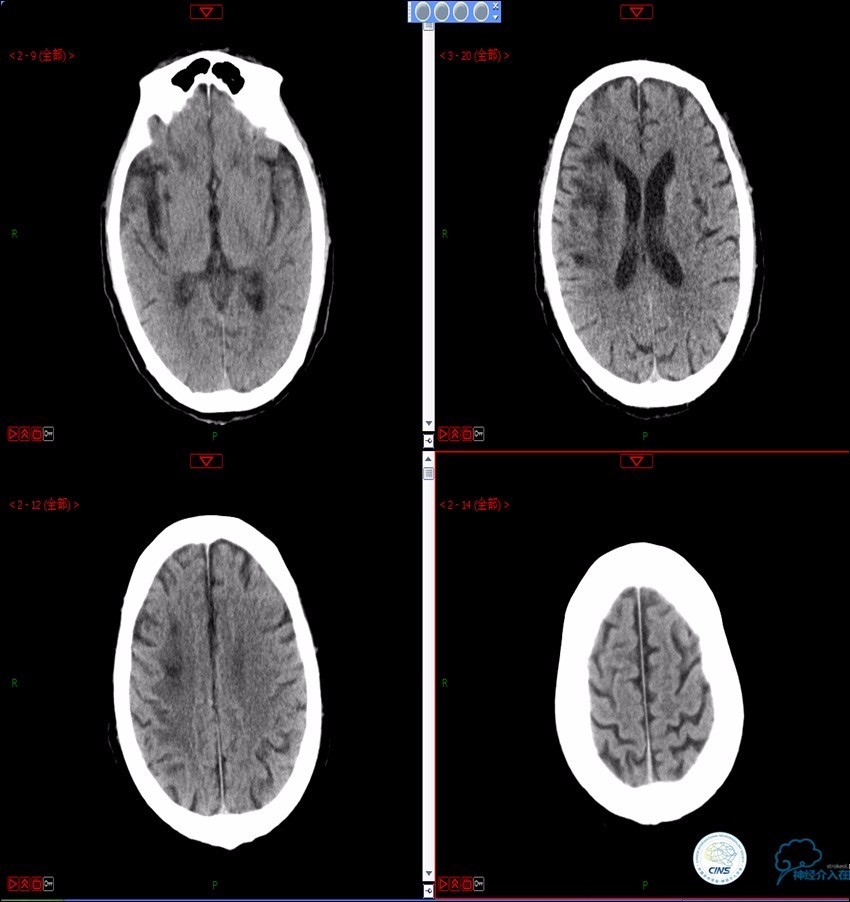

》男,74岁。

》主诉:突发左侧肢体抽搐伴口角歪斜两月余,右侧肢体抽搐三天余。

》查体:左上肢肌力Ⅲ级,左下肢肌力Ⅳ级,右侧肢体肌力Ⅴ级。

》既往史:高血压病史。

》患者术后4小时出现右侧肢体无力,伴有癫痫样症状。

》考虑小栓子脱落,术中曾有后扩。